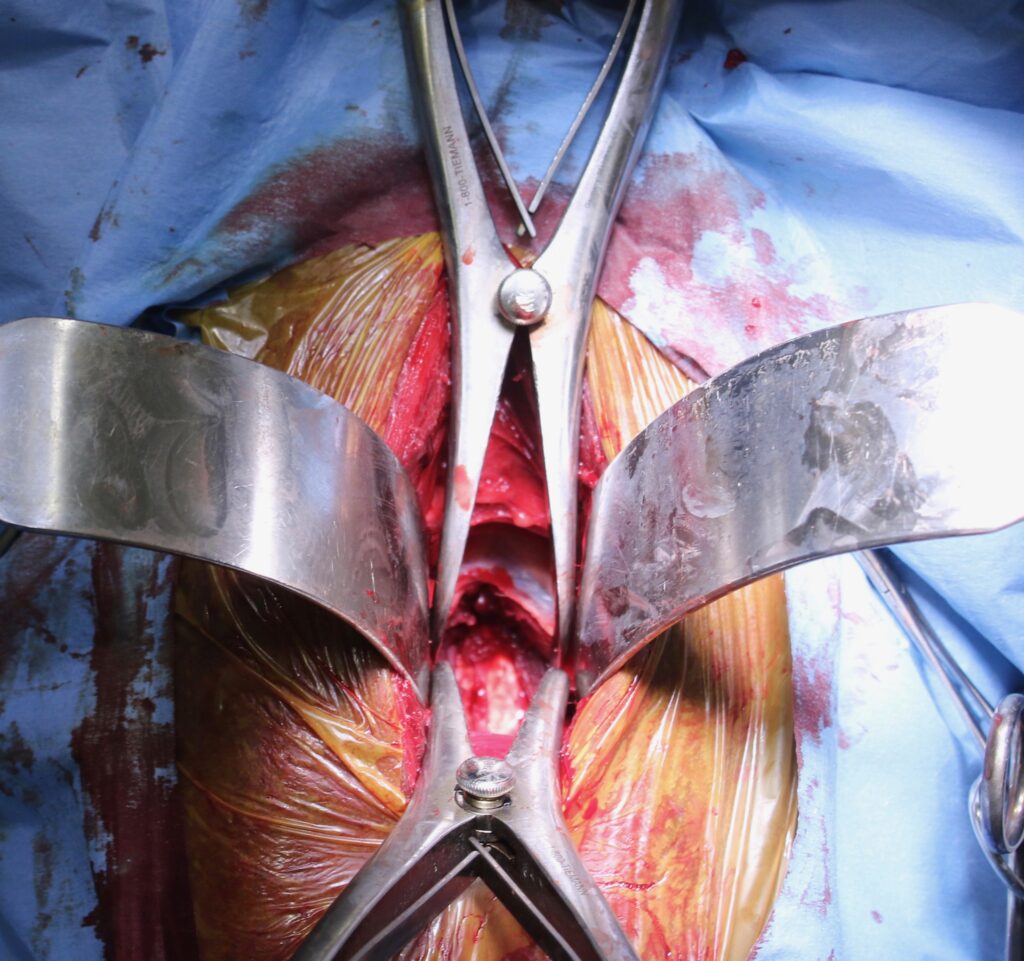

Známý dostihový kůň jménem Seattle Slew začal trpět závažnou ataxií. Dr. Grant ho operoval s použitím vylepšené protézy a kůň poté prožil ještě velmi úspěšnou dostihovou kariéru. Kůň je při artrodéze operován v celkové anestezii a je položený na zádech (obr. 10–13).

Obrázek 10: Foto z průběhu operace, 15centimetrový řez

Obrázek 11: Odtažení svalů krku pro uvolnění přístupu k obratlům

Obrázek 12: Umístění protézy tak, aby držela pohromadě oba obratle

Obrázek 13: Uzavřený řez kůží

Relativně malý, asi patnácticentimetrový řez se provádí ve spodní části krku (obr. 10) v úrovni problematického místa. Průdušnice a svaly jsou odtaženy stranou a přístup ke krčním obratlům je uvolněn (obr. 11). Titanová protéza je umístěna pod rentgenologickou kontrolou tak, aby dokonale stabilizovala oba obratle (obr. 12). Pokud se vyskytuje více míst, kde dochází ke zvýšení tlaku na míchu, je možné spojit i více obratlů (obr. 9). Tento chirurgický zákrok je v Equitomu zcela běžný a zabere přibližně jeden a půl hodiny (obr. 13).